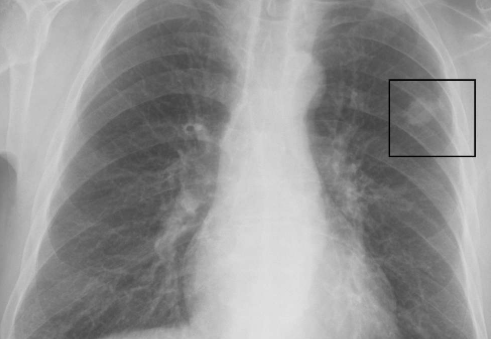

'폐결절이란' 폐 안에서 발견되는 작고 둥근 모양의 음영이나 덩어리를 말합니다. 보통 건강검진에서 흉부 CT나 X-ray를 통해 우연히 발견되는 경우가 많죠. 대부분은 3cm 이하의 크기를 가지며, 크기가 작을수록 양성(즉, 암이 아닌 경우)일 가능성이 높다고 알려져 있습니다.

- 고해상도 CT(컴퓨터단층촬영): 결절의 크기와 형태, 경계, 석회화 여부 등을 더 정밀하게 관찰

실제로 저도 고해상도 CT를 한 번 더 찍은 뒤, 결절의 변화 여부를 확인하기 위해 6개월 후 재검을 권유받았습니다. 매일매일 불안하게 기다리는 건 아니었지만, 가끔 생각날 때마다 마음이 무거웠던 건 사실이에요. 하지만 의사 선생님이 "작고, 경계가 뚜렷하며, 모양이 균일한 경우 대부분은 문제가 없다"고 말씀해주셔서 많이 안심됐습니다.